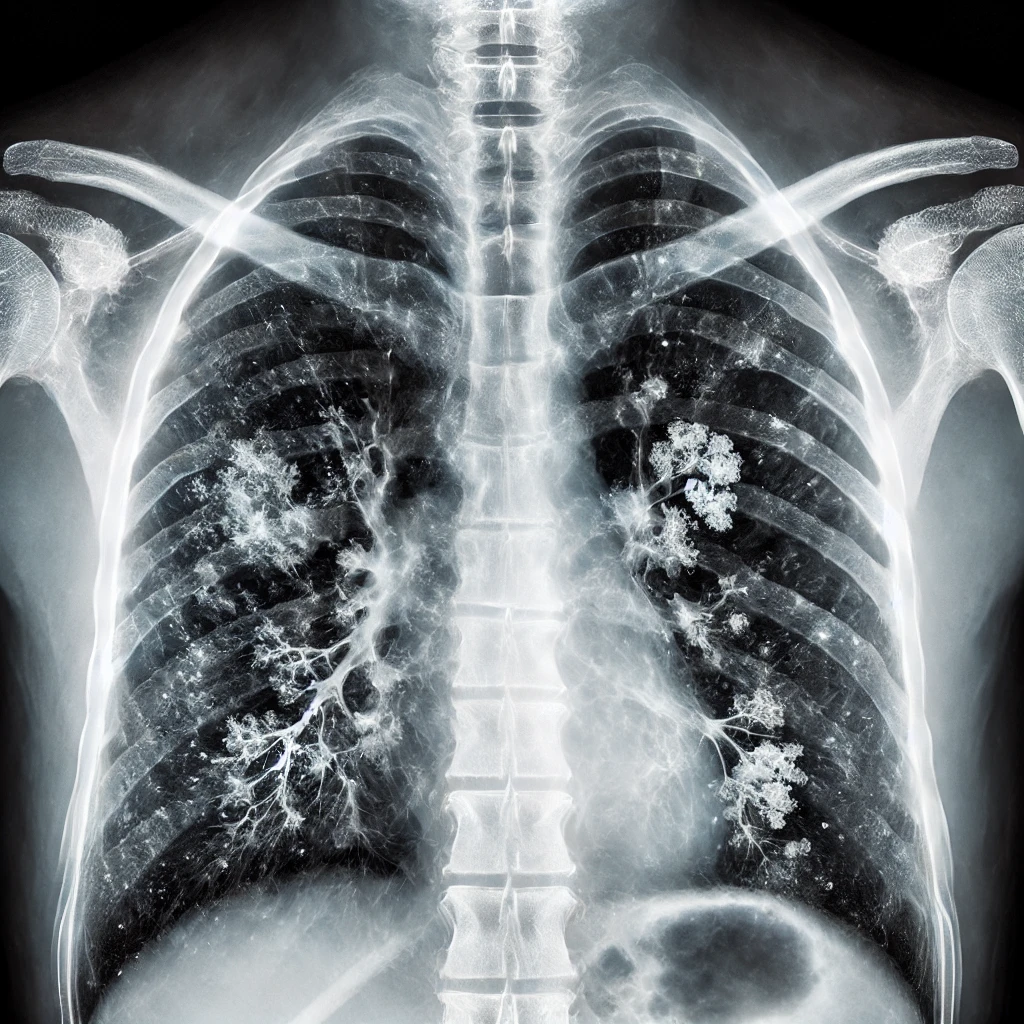

마이코플라즈마(Mycoplasma)는 최근 들어 건강을 위협하는 주요 병원체로 급부상하고 있습니다. 작은 세균 하나가 사람의 폐를 감염시키고, 자칫하면 심각한 폐렴으로 이어질 수 있다는 사실을 알고 계셨나요? 심지어 이 세균은 기존 항생제에도 잘 반응하지 않기 때문에 치료 시점이 늦어지면 고통스럽고 긴 치료가 필요할 수 있습니다.

최근 발표된 세계 보건기구(WHO)의 보고서에 따르면, 호흡기 질환 환자 중 마이코플라즈마에 의한 감염이 해마다 증가하고 있는 것으로 나타났습니다. 특히 면역력이 약한 중장년층에게 치명적일 수 있는 이 감염은 적절한 시기에 치료하지 않으면 더 심각한 합병증으로 이어질 수 있습니다.

"이 감염을 방치하면, 당신의 폐 건강에 심각한 타격을 줄 수 있습니다. 치료 시기를 놓치지 마세요!"